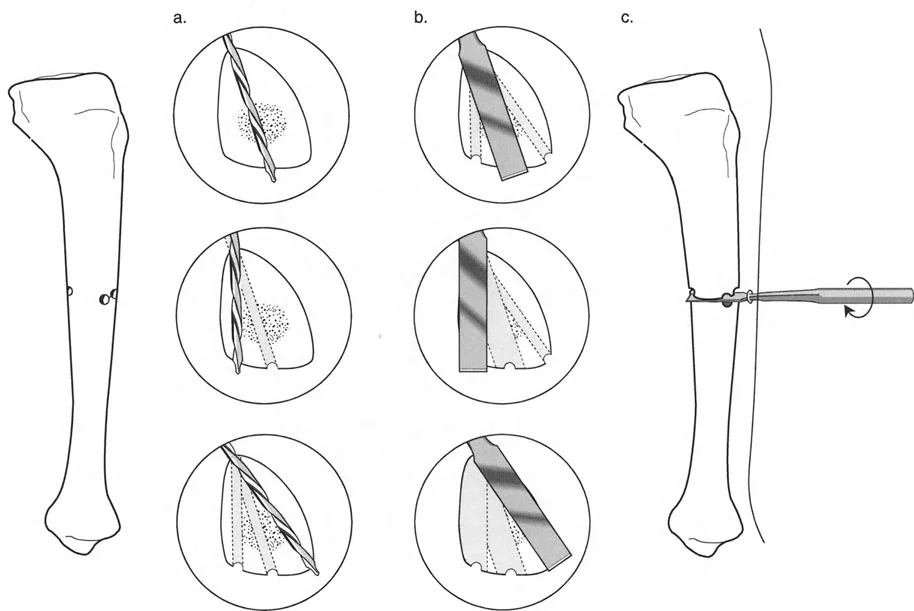

قواعد بالي لقطع العظم (Osteotomy Rules) في وضع الأجهزة

فهم قواعد بالي لقطع العظم أمر لا غنى عنه لتخطيط الإطار:

- قاعدة قطع العظم 1: عندما يمر قطع العظم ومحور تصحيح الانحراف (ACA) كلاهما عبر مركز دوران الانحراف (CORA)، فإن نهايات العظم ستنحرف دون ترجمة (انزياح). يتم استعادة المحور الميكانيكي، وتظل نهايات العظم متقاربة تمامًا، مما يخلق تصحيحًا كلاسيكيًا "إسفينيًا مفتوحًا" أو "إسفينيًا مغلقًا".

- قاعدة قطع العظم 2: عندما يمر محور تصحيح الانحراف (ACA) عبر مركز دوران الانحراف (CORA)، ولكن يتم إجراء قطع العظم على مستوى مختلف (غالبًا بسبب ضعف جودة العظم عند CORA أو مشاكل في الجلد)، فإن نهايات العظم ستنحرف وتخضع لترجمة محسوبة ومقصودة لإعادة محاذاة المحور الميكانيكي.

- قاعدة قطع العظم 3: (للاكمال) عندما يمر قطع العظم عبر مركز دوران الانحراف (CORA)، ولكن يتم وضع محور تصحيح الانحراف (ACA) خارج CORA، سيتم إنشاء تشوه ترجمة جديد، وهو خطأ شائع في وضع المفصلات غير المخطط له جيدًا.

في المنشآت القريبة من المفصل، غالبًا ما نعتمد على قاعدة قطع العظم 2. نظرًا لأنه لا يمكننا قطع العظم بأمان عند خط المفصل تمامًا (مركز دوران الانحراف CORA)، فإننا نقطع العظم في مستوى أدنى في منطقة الميتافيسيس. بعد تحقيق التصحيح الزاوي عبر المفصلات (محور تصحيح الانحراف ACA)، يتم إعادة محاذاة خطوط المحور الميكانيكي بشكل مثالي، ولكن نهايات العظم في موقع قطع العظم تتحرك بالنسبة لبعضها البعض.